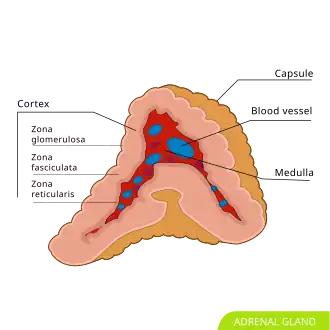

Adrenal gland; the medulla (center, red) is the origin of the pheochromocytoma.

There is an adrenal gland, highlighted in yellow, on top of each of the kidneys.